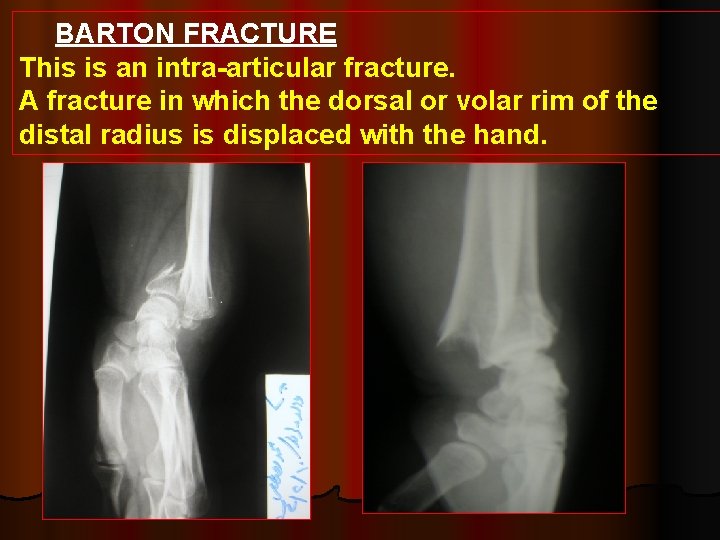

BARTON FRACTURE This is an intra-articular fracture. A fracture in which the dorsal or volar rim of the distal radius is displaced with the hand.